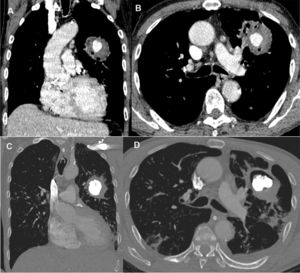

A 65-year-old man recently diagnosed with pulmonary tuberculosis presented to the emergency department due to cough and daily hemoptysis episodes (50–100ml blood/episode). While hospitalized, he experienced a severe massive bleeding episode, prompting emergency fiberoptic bronchoscopy that revealed a clot obstructing the left main bronchus. Chest computed tomography demonstrated the presence of a round opacity in the left upper lobe, with a nodular formation with intense contrast uptake inside, compatible with Rasmussen aneurysm (RA; Fig. 1A and B). The patient underwent angiography of the pulmonary and bronchial arteries, which did not demonstrate aneurysmal formation. Ultrasound-guided aneurysmal sac puncture using a 22G Chiba needle and percutaneous embolization with a cyanoacrylate/Lipiodol® solution under fluoroscopic visualization were performed. The RA was adequately filled with embolizing material (Fig. 1C and D). The patient was discharged 3 days after the procedure, and was completely asymptomatic after 1 year of follow up. Tuberculosis is a significant cause of hemoptysis globally, especially in developing countries, and RA is a rare but life-threatening complication. For most cases of RA, especially those with life-threatening hemoptysis, safer and less-invasive endovascular therapy with embolization has replaced surgical intervention. In some cases, however, percutaneous injection therapy can be considered because embolization of the pulmonary or bronchial arteries alone may fail to control the hemoptysis.1,2

Enhanced coronal (A) and axial (B) computed tomography images showing an inhomogeneous round opacity in the left upper lobe, with a nodular formation showing intense contrast uptake inside, compatible with Rasmussen's aneurysm. Enhanced coronal (C) and axial (D) computed tomography images acquired 48h after treatment demonstrated the adequate filling of the Rasmussen's aneurysm with embolizing material, with no indication of new bleeding.